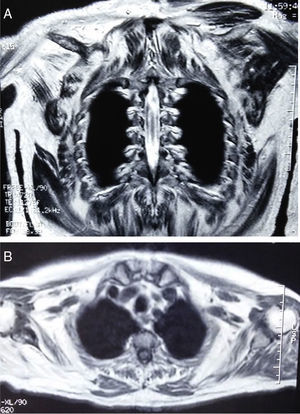

Clinical ObservationsCase report no. 1. The patient was a 72-year-old man with Paget's disease who was being followed in periodic visits to the rheumatology outpatient clinic. Although he had no symptoms of muscle involvement, an elevated CK level was an incidental finding in a routine analysis. A review of previous analyses revealed that it had been rising progressively, and had reached values of 5000IU/L. He also had slightly elevated aldolase levels, with no changes in liver enzymes or thyroid status, and negative autoantibody tests. Physical examination showed normal muscle balance. An electromyogram (EMG) revealed no evidence of myopathy. Magnetic resonance imaging (MRI) of the shoulder girdle showed bilateral atrophy and fatty replacement in several muscles (Fig. 1A and B). It also revealed changes in the deltoid muscle, which was biopsied. The pathological study disclosed the presence of subsarcolemmal glycogen-containing vacuoles (Fig. 2A and B). Histochemical analysis demonstrated a total absence of myophosphorylase, a finding compatible with McArdle disease. In the genetic study, a homozygous Y733X nonsense mutation was observed in exon 18 of the PYGM gene. The patient was referred to the endocrinology-nutrition department.

The characteristic laboratory findings are elevated CK levels (even during intervals between peaks in disease activity).2,3,5 The EMG can be normal or show evidence of myopathy.5 If the ischemic forearm exercise test is performed, the curve observed for lactic acid is flat, indicative of failure of the breakdown of glycogen to lactate.5,14 Regarding imaging studies, both computed tomography and MRI can demonstrate atrophy and fatty replacement in muscle, especially in cases involving late onset, as in our first patient.12,15 The definitive diagnosis is based on muscle biopsy and the observation of the absence of myophosphorylase in a subsequent immunohistochemical analysis.3,5 The histological findings are characterized by the presence of subsarcolemmal vacuoles containing glycogen, which can be examined using periodic acid Schiff (PAS) staining.3 The diagnosis should be corroborated by a genetic study.3,5,6,8